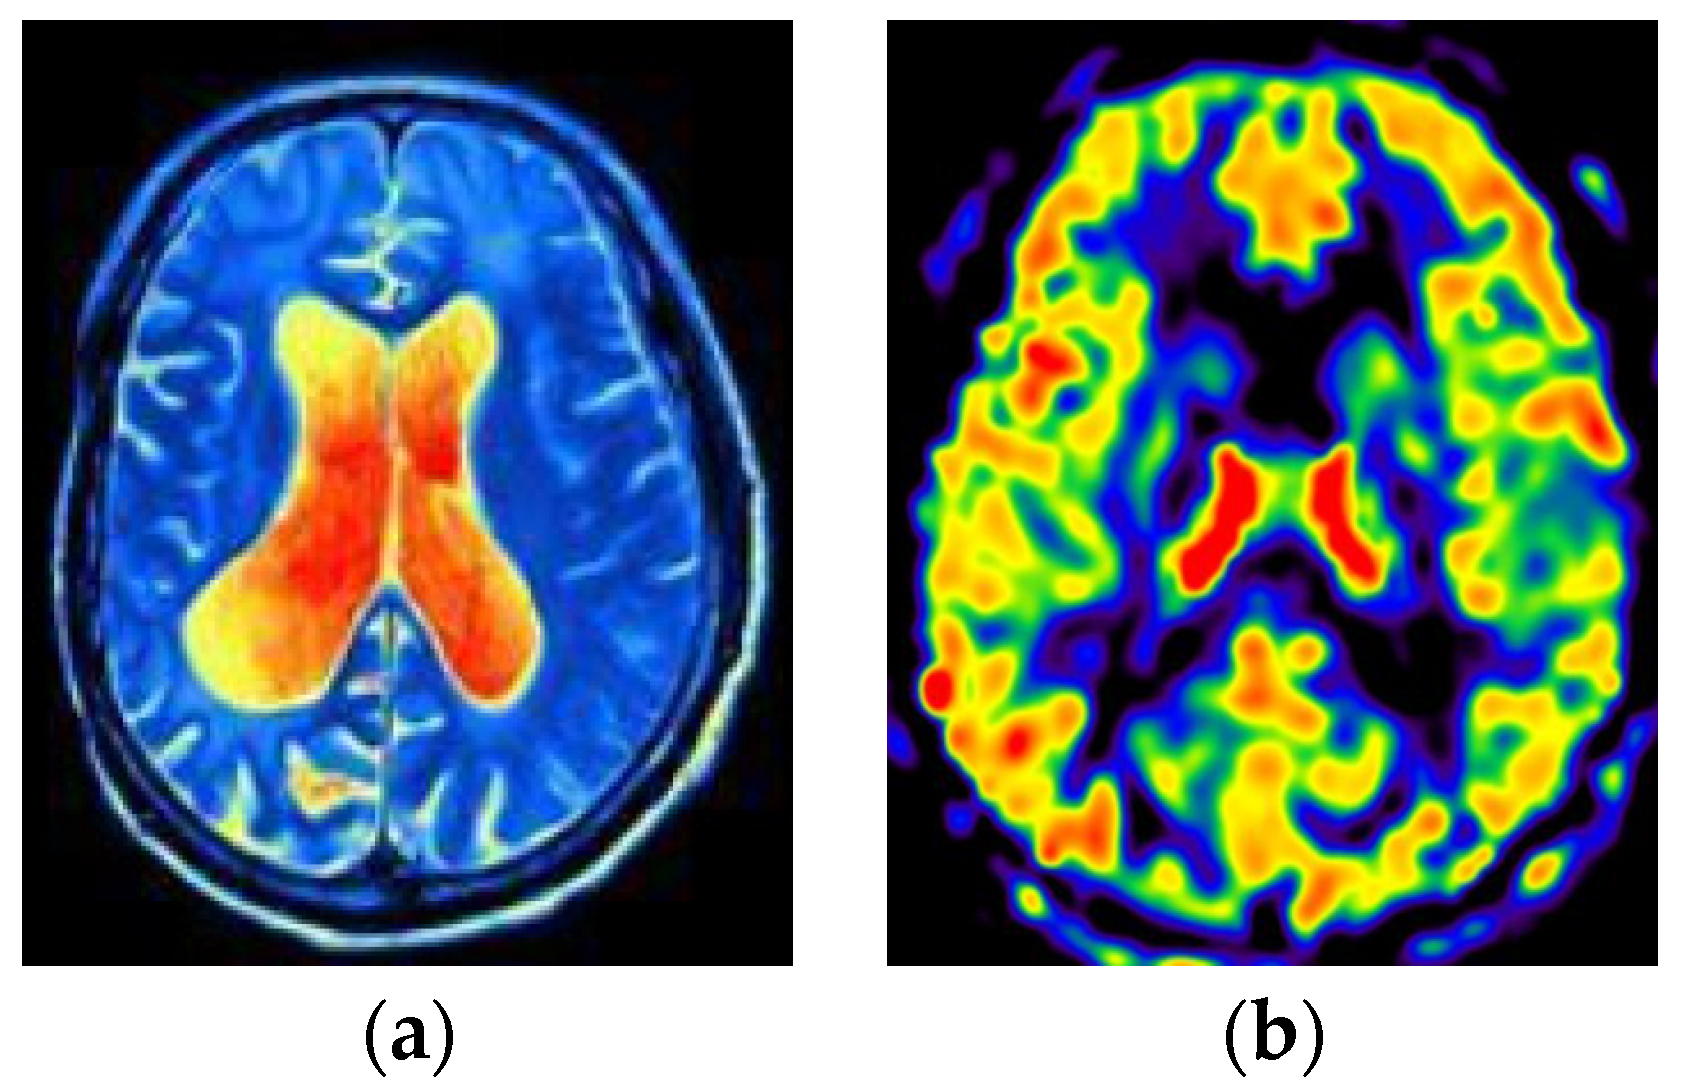

2. Data and Methods

2.2. Data Preprocessing

3.4. Data Visualization and Analysis